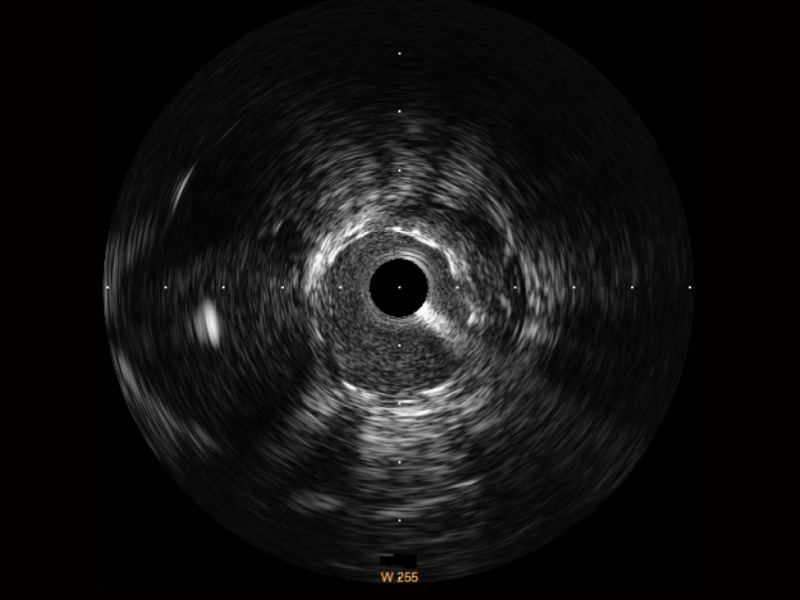

治療前后兩次測量錄像對比

簡化療效評估

一鍵智能描跡,自動測量斑塊負(fù)荷、面積狹窄率等指標(biāo),準(zhǔn)確率高于90%